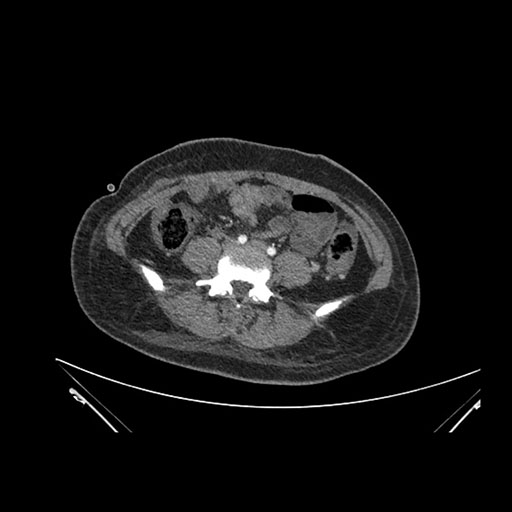

Axial Arterial

Axial Venous